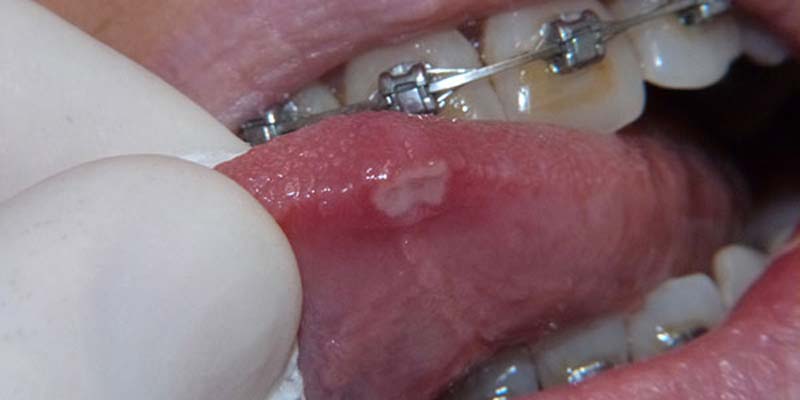

Le afte della bocca , rientranti nel capitolo delle cosiddette stomatiti, processi infiammatorii che coinvolgono la cavità orale e la mucosa della bocca, sono probabilmente, insieme all'herpes labiale, le forme, appunto, di stomatite più contratte. Si presentano come piccole lesioni della mucosa della cavità orale (guance, labbra e, talvolta, anche sulla lingua) che hanno l'aspetto di piccole ulcerazioni biancastre, di forma tondeggiante, che sono spesso causa di bruciori e forti dolori, in particolare durante l'atto masticatorio. Nella grande maggioranza dei casi le lesioni aftose si presentano isolate ma, sporadicamente, possono presentarsi anche in piccoli gruppi ed associarsi a sintomi quali febbre, ingrossamento dei linfonodi ed anche sintomi influenzali.

Si distinguono clinicamente una forma “ Minor” , caratterizzata da lesioni di piccola dimensione , in genere non superiori ad un cm che si localizzano generalmente a livello della mucosa orale non cheratinizzata, (vestibolo orale, ventre linguale, pavimento orale, mucosa labiale). La guarigione è spontanea e avviene con restituito ad integrum dei tessuti in un paio di settimane dall’esordio, ed una forma “ Major”, in cui le ulcere hanno un diametro che può raggiungere e superare il centimetro, guariscono in tempi più lunghi rispetto alle afte minor e spesso lasciano una cicatrice, la mucosa interessata è quella del palato o del dorso linguale. Come già accennato le afte vanno incontro ad una guarigione spontanea nel giro di sette dieci giorni e il trattamento, ad oggi , è indirizzato al solo scopo di ridurre la sintomatologia e abbreviare il decorso delle lesioni; si avvale classicamente dell’utilizzo di preparati per uso topico a base di corticosteroidi, di aloe, di sodio jaluronato e aminoacidi o di antisettici (per evitare la sovrainfezione della mucosa lesionata). Un’arma in più è rappresentata dall’uso del laser a diodi , che ha dimostrato di ottenere ottimi risultati , grazie alla sua capacità di sterilizzazione dei tessuti infetti e di stimolazione del processo di guarigione, tale cherisulta essere, attualmente, lo strumento ideale per la terapia di queste dolorosissime lesioni, che, se trattate nel giro di 24 ore o poco più, hanno una rapidissima remissione ed un’immediata riduzione della sintomatologia dolorosa.